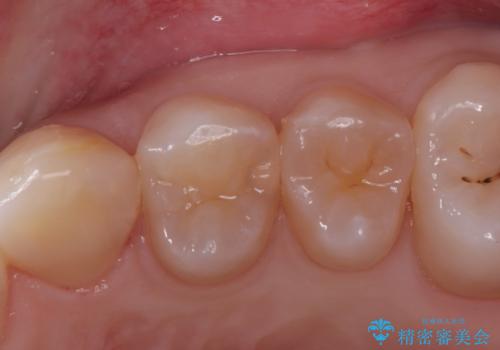

奥歯を美しくセラミック修復

左上7のメタルインレーを除去|セラミッククラウンで自然な美しさと機能回復